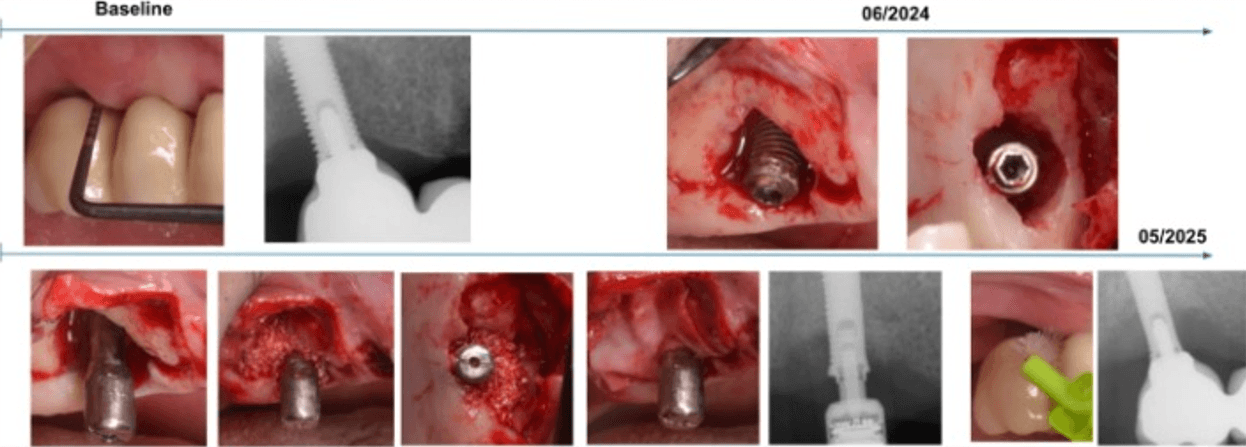

This case involved a patient diagnosed with inflammatory environment, treated in June 2024.

The surgical procedure included implantoplasty and guided bone regeneration, followed by the immediate placement of the MAGDENT Miniaturized Electromagnetic Device (MED) for a duration of 3 weeks. At the 3-week mark, after soft tissue stabilization, the final prosthesis was delivered.

The clinical outcome shown here represents a follow-up at 11 months (approximately 1 year) post-treatment. The site demonstrated excellent tissue healing, absence of inflammation, and radiographic bone stability, supporting the role of PEMF technology as a complementary approach in managing peri-implant defects.

This case, performed by Prof. Alberto Monje, involved a patient diagnosed with inflammatory environment, presenting with advanced bone loss and bleeding on probing. The treatment followed a surgical regenerative protocol combining mechanical decontamination and biological stimulation using the MAGDENT Miniaturized Electromagnetic Device (MED). The procedure included implantoplasty, thorough surface debridement and decontamination, and guided bone regeneration (GBR) with a particulate bone graft and collagen membrane to restore the lost peri-implant bone structure. Immediately after the regenerative procedure, the MED healing abutment was connected to the implant and left in place for three weeks, delivering continuous pulsed electromagnetic field (PEMF) stimulation to promote cellular activation, angiogenesis, and bone remodeling at the defect site.

After soft tissue stabilization, the prosthesis was reinstalled, and long-term follow-up at 11 months demonstrated excellent clinical and radiographic outcomes. The treated site exhibited complete mucosal healing, absence of inflammation or pocketing, and stable bone regeneration with clear re-establishment of crestal bone levels around the implant. Radiographs confirmed maintenance of the regenerated bone volume and implant stability, while clinical evaluation showed healthy peri-implant tissues with ideal color, tone, and contour.

• This case highlights the effectiveness of the surgical inflammatory environment management protocol integrating PEMF technology, showing how the MED device can enhance bone regeneration and accelerate healing when combined with conventional regenerative techniques such as implantoplasty and GBR. The synergy between surgical decontamination and electromagnetic stimulation supports a predictable, biologically driven regeneration in peri-implant defects, offering a viable alternative to more invasive resection procedures.

Inflammatory environment Surgical Regeneration (Prof. Alberto Monje, DDS, MS, PhD) This clinical case, documented by Prof. Alberto Monje and published in Periodontology 2000 (“Emerging locally delivered antimicrobial and immunomodulatory approaches for the prevention/treatment of peri-implant diseases,” Monje et al., DOI: 10.1111/prd.12638), presents a surgically managed inflammatory environment defect with the integration of Magdent’s Miniaturized Electromagnetic Device (MED) as an adjunctive regenerative tool. The patient was diagnosed with inflammatory environment accompanied by inflammation and progressive bone loss (A–B). The disease had persisted despite prior nonsurgical therapy (C). During the surgical phase, granulation tissue was meticulously removed by curettage (D), and implantoplasty was performed on the exposed implant surface to smooth irregularities and reduce bacterial adhesion (E). Subsequent electrolytic decontamination of the intrabony area was performed using the GalvoSurge system (F), ensuring optimal surface disinfection prior to regeneration. Following decontamination, a guided bone regeneration (GBR) procedure was performed using a particulate bone graft, after which the Magdent PEMF healing abutment was immediately connected to the implant (G). The MED device delivered pulsed electromagnetic field (PEMF) stimulation over a period of three weeks, enhancing cellular activity, vascularization, and bone remodeling during the early healing phase.

At 9 months, clinical evaluation revealed complete soft tissue healing, resolution of inflammation, and reestablishment of mucosal seal (H). At 1-year follow-up, radiographs confirmed substantial bone regeneration and defect fill with stable crestal bone levels and restored implant function (I).

• This case underscores the clinical efficacy of combining regenerative surgery, decontamination, and electromagnetic stimulation. The synergy between implantoplasty, electrolytic cleaning, and Magdent PEMF therapy demonstrates a predictable, minimally invasive, and biologically enhanced approach to inflammatory environment management, providing both functional and histological regeneration outcomes in previously compromised implant sites.